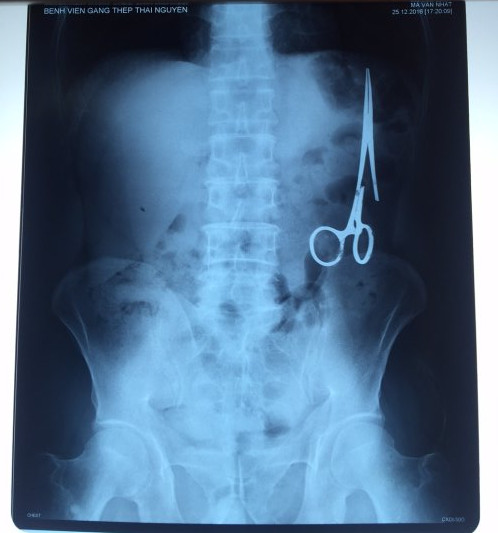

遺留在病人腹中的剪刀

據(jù)越南青年報1月2日報道,在越南首都河內(nèi)醫(yī)療專家的幫助下,越南東北部的太原?。═hai Nguyen)鑄鋼醫(yī)院的醫(yī)生日前從54歲患者M.V.N腹中取出一把醫(yī)用剪刀。這把剪刀是此前曾為M.V.N手術的醫(yī)生遺留的,已經(jīng)在其腹中待了18年時間。

醫(yī)務人員表示,這把剪刀遺留在病人腹部左側,與結腸緊挨著。剪刀的把手已經(jīng)生銹,部分器官也已經(jīng)與剪刀粘連起來。但在過去多年中,M.V.N沒有任何不適感覺,也從未因為留在腹中的剪刀引發(fā)的相關問題去看過醫(yī)生。直到2016年12月,M.V.N因為遭遇了一場車禍,才到鑄鋼醫(yī)院進行身體檢查。

超聲波檢查顯示,M.V.N的腸子中有個奇怪物體,看起來就像醫(yī)用剪刀。M.V.N證實,他曾于1998年6月份在北江省綜合醫(yī)院接受手術,在此后也從未進行過任何手術。近來,他感到腹部有些疼痛,并試圖通過服用藥物治療。12月27日,M.V.N回到北江省綜合醫(yī)院再次進行超聲波檢查,顯示其腹部的確存在怪異物體。